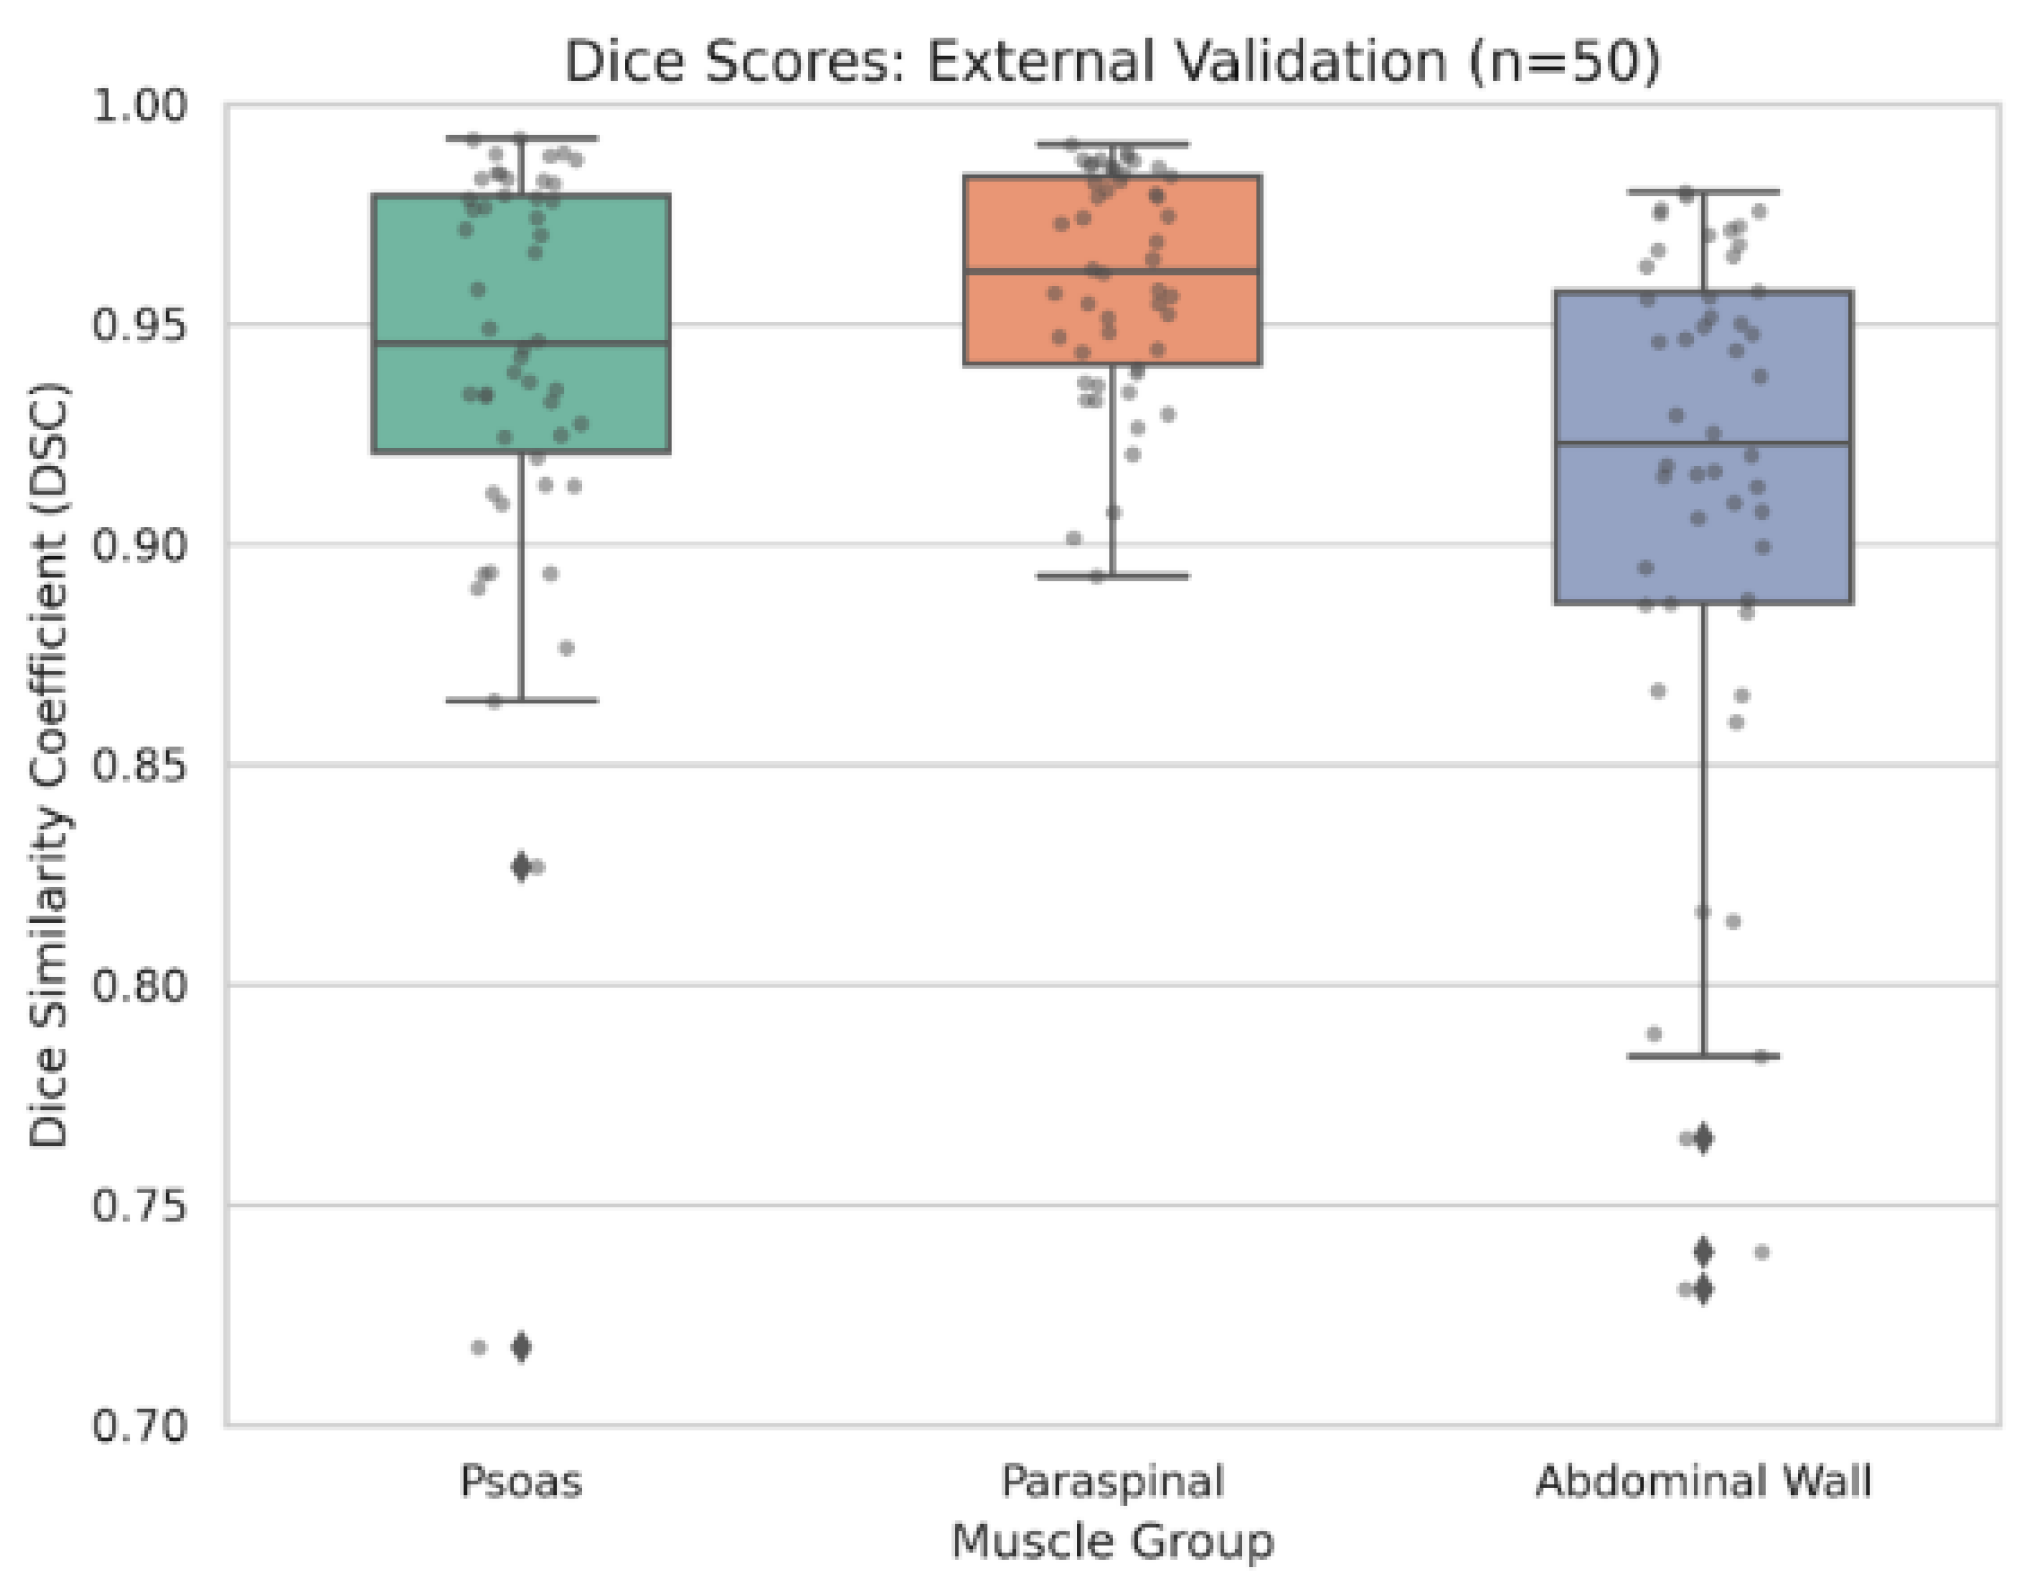

3.2. External Validation and Ensemble Efficacy

| Metric | Single fold (Fold 4) | 5-fold ensemble | P-value |

|---|---|---|---|

| Overall mean DSC | 0.937 | 0.937 | 0.736 |

| Psoas DSC | 0.939 | 0.941 | 0.448 |

| Paraspinal DSC | 0.960 | 0.960 | 0.810 |

| Abdominal wall DSC | 0.912 | 0.911 | 0.858 |

| Minimum observed DSC | 0.720 | 0.822 | — |